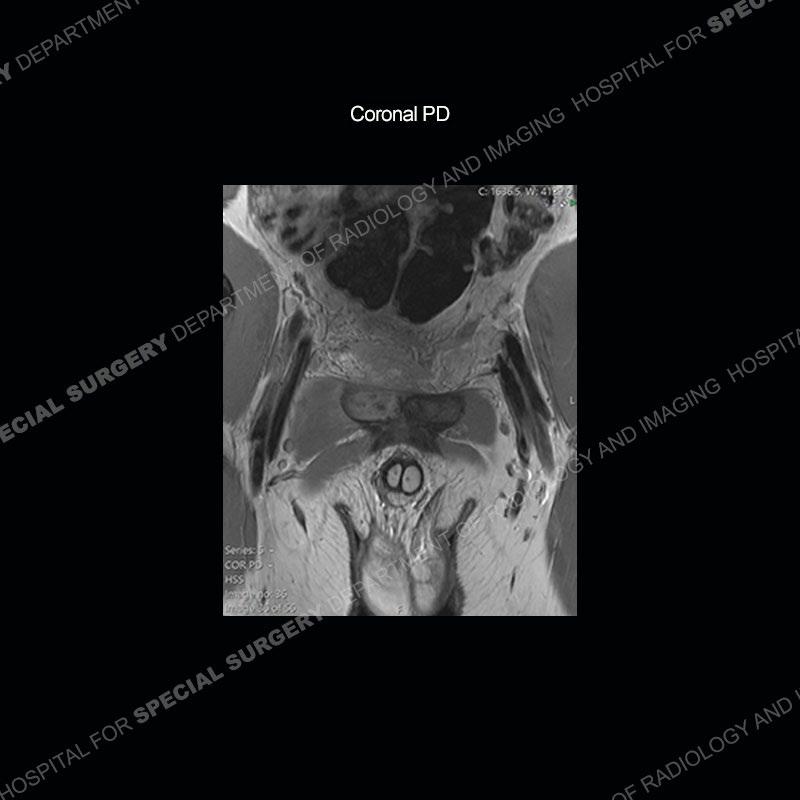

Radiographs did not demonstrate any clear abnormality. The MRI shows markedly abnormal signal of the right superior pubic ramus and abnormal signal/”mass” extending into the adjacent soft tissue. The inferior articular surface of the ramus showed what was thought to be bony destruction. CT examination shows a destructive process of the right superior pubic ramus.

Subsequent MRI in a very short time interval shows markedly increased abnormality of the ramus and increased edema and “mass” of the soft tissue. Post contrast imaging shows multiple, rim enhancing collections of the soft tissue and similar albeit less conspicuous enhancing collection of the ramus.

This case was a bit surprising to all involved given that the young man is otherwise in good health and extremely active in sports. The original thought was this case was going to be an overuse injury or stress fracture. The pubic ramus with the adjacent physis acts as a metaphyseal equivalent and although not frequently thought of would be a reasonable location for infection/osteomyelitis. The first MRI was somewhat confusing as the process did not have an appearance of a stress injury or rectus adductor aponeurosis injury. The degree of edema of the bone and soft tissue together would be odd especially for a sports hernia process. Initially, the thought was of an aggressive process which could be infection or neoplastic. Particularly, the abnormal architecture of the inferior surface of the ramus looked like a destructive process.

The repeat MRI, with the marked degree of increased abnormality of the bone and soft tissue shifted the diagnosis to a high degree towards infection. Even the most aggressive of neoplasms would not have that the degree of change in a 3-day time span. The CT study was shown before the repeat MRI but actually occurred just after the repeat MRI. It helped confirm the destructive process of the ramus and particularly the abnormal architecture along the inferior margin. The patient went on to have a CT guided aspiration of one of the soft tissue collections with 4cc of purulent fluid obtained. A surgical irrigation and debridement of the bone and soft tissue was performed. A PICC line was placed and the patient is currently undergoing IV antibiotic treatment with a possible repeat irrigation and debridement.